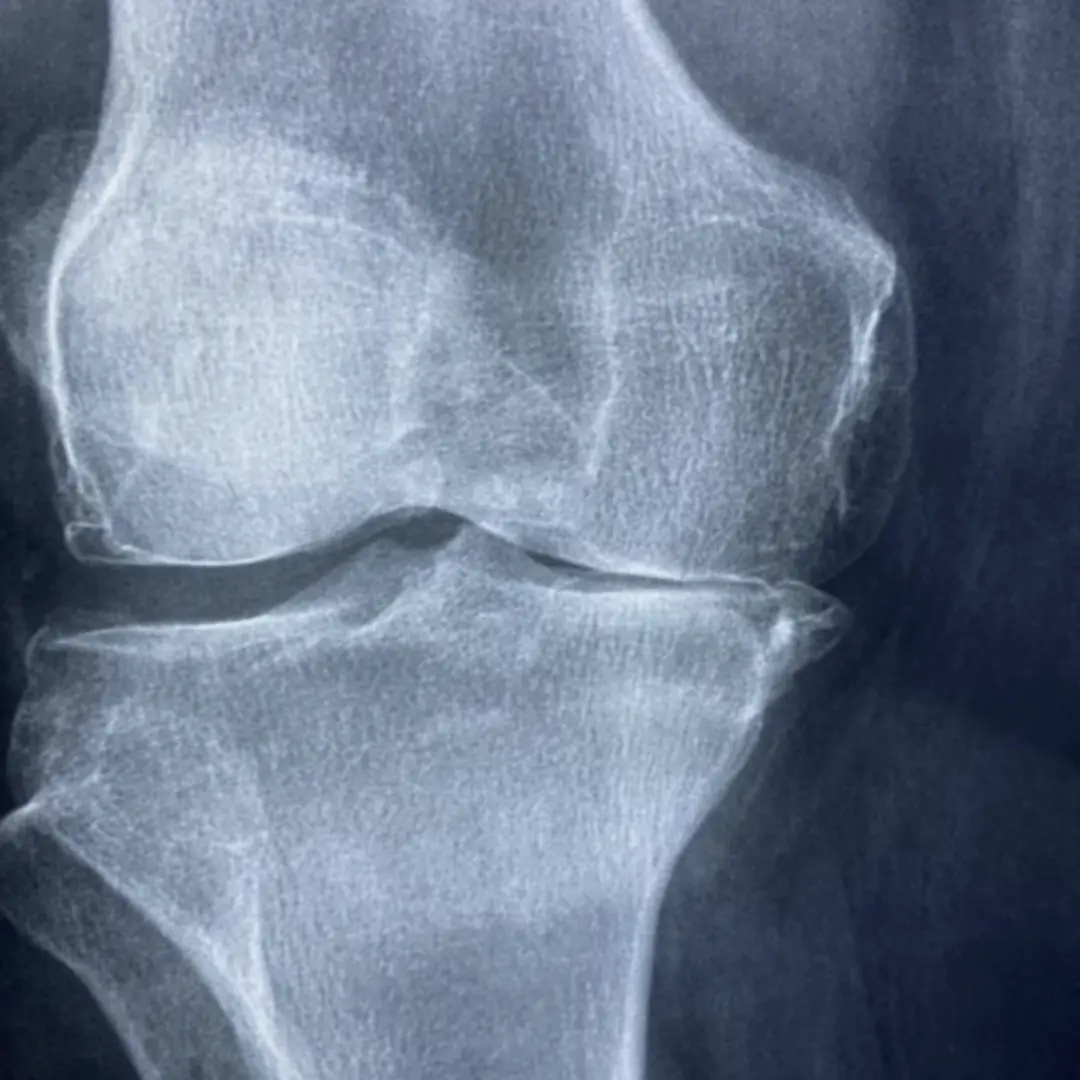

- 골관절염 (퇴행성 관절염) 환자: 관절 연골 손상으로 인한 염증과 통증 완화에 오메가-3 지방산이 풍부한 등푸른 생선이나 항염 효과가 있는 강황 등이 도움을 줄 수 있어요.

- 류마티스 관절염 환자: 자가면역 질환으로 인한 관절 염증 완화에 오메가-3 지방산, 강황, 올리브 오일 등이 도움을 줄 수 있으며, 면역력 강화에 좋은 마늘 섭취도 고려해 볼 수 있습니다.

- A2. 위에 소개된 음식들은 주로 항염 효과를 가지고 있어 골관절염, 류마티스 관절염 등 다양한 종류의 관절염 증상 완화에 도움을 줄 수 있습니다. 하지만 특정 종류의 관절염에 더 효과적인 음식도 있을 수 있으므로, 전문적인 상담을 통해 자신에게 맞는 식단을 구성하는 것이 좋습니다.